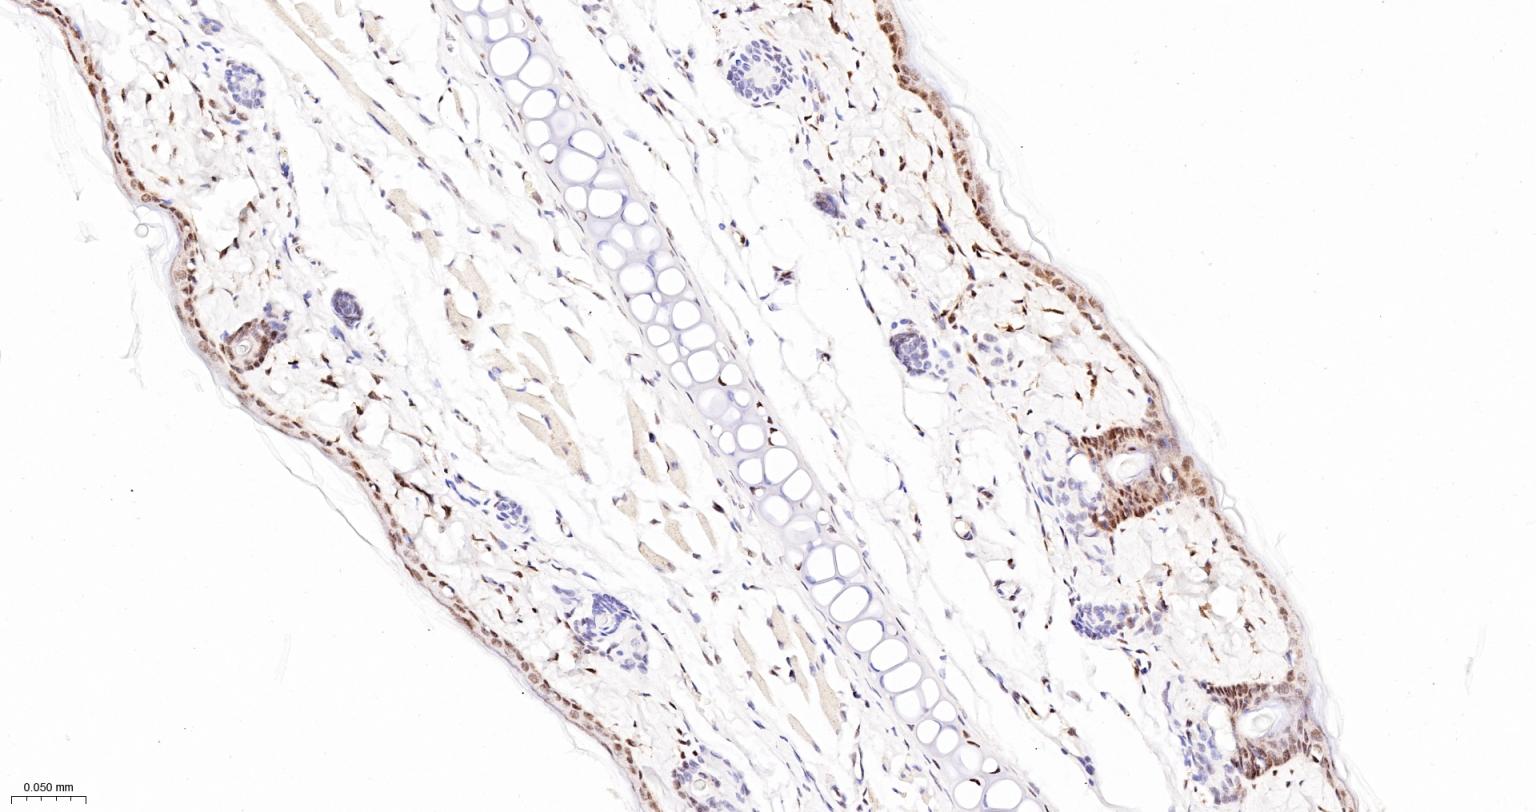

Paraformaldehyde-fixed, paraffin embedded Rat Skin; Antigen retrieval by boiling in sodium citrate buffer (pH6.0) for 15 min; The section was incubated with phospho-UBF1(Ser484) Monoclonal Antibody, Unconjugated (bsm-63010R) at 1:200 overnight at 4°C, followed by conjugation to the bs-0295G-HRP and DAB (C-0010) staining.